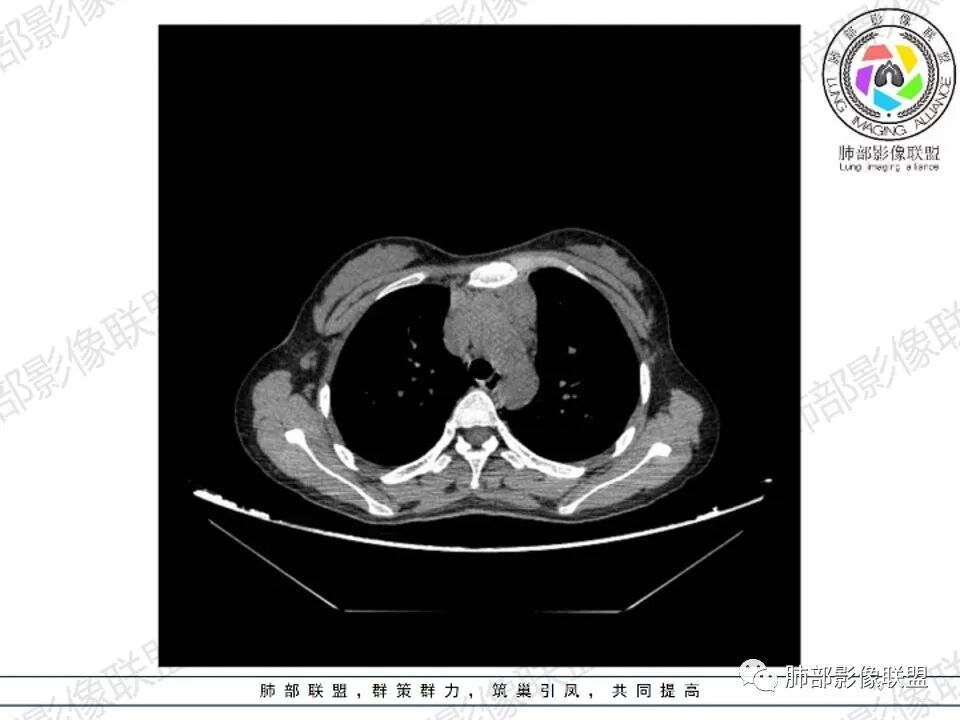

病灶两叶,相对独立,中央相连

整体还是胸腺的形态

边缘平直为主,稍膨隆,但是无明显的局限性凸起

囊变区域弥漫,大部分直达壁,分界不清,部分分界清楚

内部血管走形自然

多发淋巴结肿大

问题:胸腺区病变,从形态、分叶,判断胸腺来源病变应该没问题